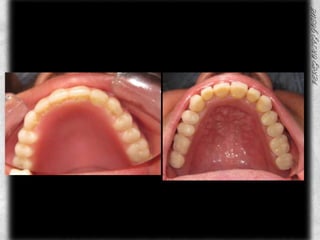

COMPARATIVOS

ARCADA SUPERIOR CLASIFICACIÓN DE OSAWA TIPO IFORMA DE PROCESO “U”LINEA MEDIA COINCIDE CON EL RAFE PALATINOCOLOR ROJO BRILLANTETEXTURA LISAPROCESO ALVEOLAR TIPO IAPARENTEMENTE SIN PRESENCIA DE CANDIDABUENA INSERCION DE LOS FRENILLOS

ARCADA INFERIORSIN PRESENCIA DE ORGANOS DENTARIOSCOLORACION ROSABUENA INSERCION DEL FRENILLO LINGUAL PROCESO ALVEOLAR TIPO IIISIN PRESENCIA DE CANDIDASIN ULCERACIONES